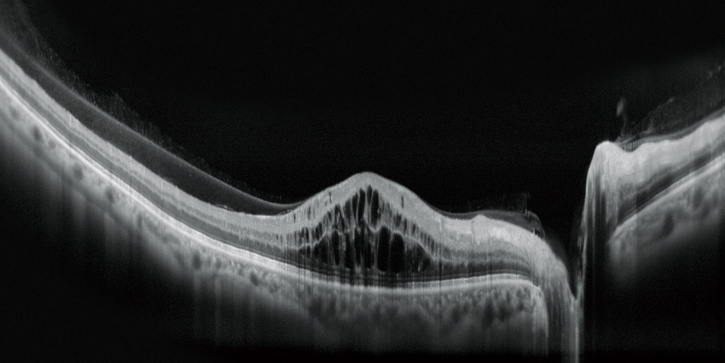

高清廣域OCT*

Mirante的掃描區域可達16.5 x 12毫米,單次拍攝就可實現包括黃斑和視盤的廣域診斷。超精細模式和高清自動追蹤功能可提供從玻璃體到脈絡膜的高質量圖像來觀察細微的病理改變。

* 適用于SLO/OCT型。

Fly同步瀏覽功能

Fly同步瀏覽功能可滾動查看同一區域不同模式的影像,極大地提高了多模態成像的實用性。